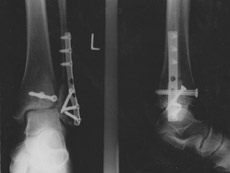

Für die nächsten sechs Wochen sind Rollstuhl und Krücken angesagt...